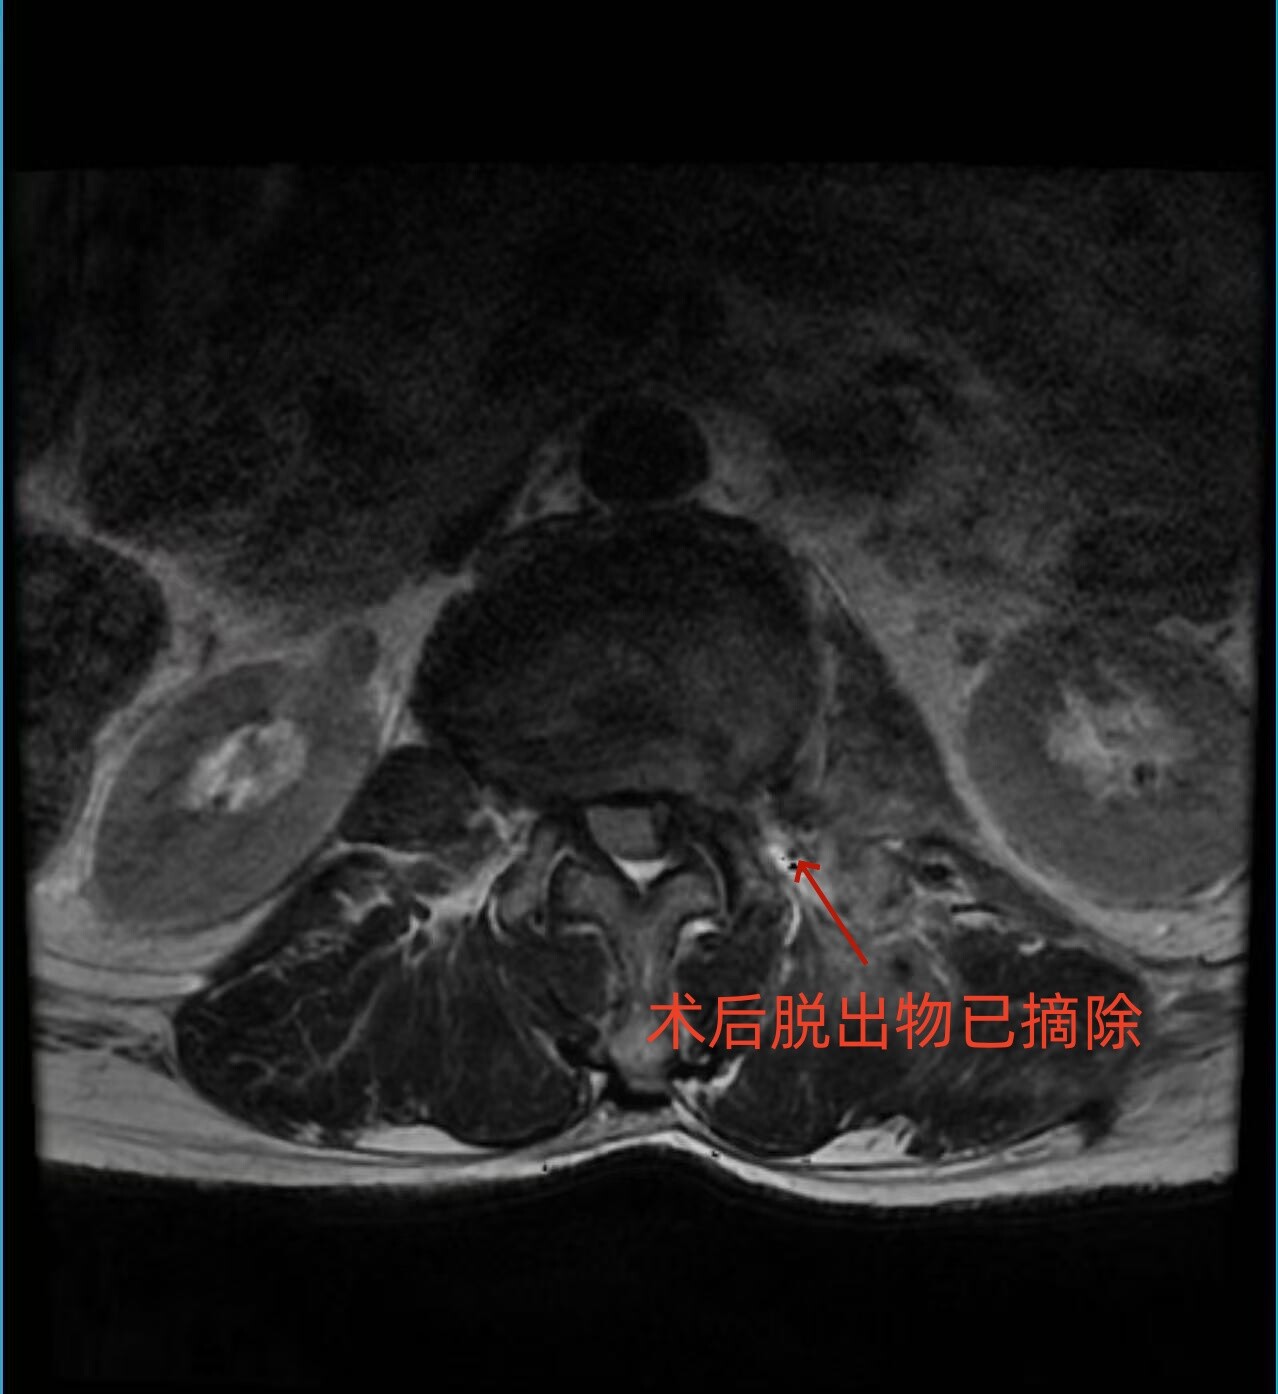

患者慕名来到永兴县人民医院骨二科。接诊后,医生团队通过详细查体和腰椎MRI检查,明确诊断为“腰椎间盘突出症(腰2/3、脱出型)”。检查显示,脱出的髓核组织不仅存在于椎管内,还延伸至椎间孔及椎间孔外,严重压迫左侧腰2出口神经根,这正是患者剧烈疼痛、无法行走的根本原因。

术后,患者左侧大腿前方的剧烈疼痛完全消失,肢体活动恢复正常。术后第二天,患者即可下地行走自如,精神状态明显好转。复查腰椎MRI显示,压迫神经根的髓核已被彻底摘除,神经根压迫完全解除。